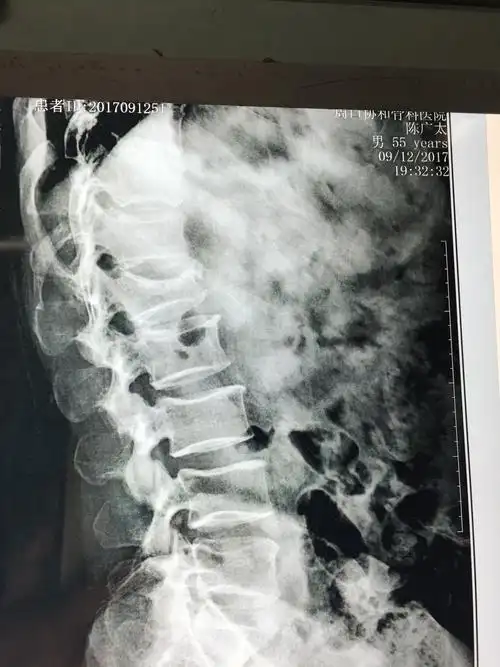

术前x线平片示腰2椎体明显压缩骨折,压缩约1/2.

腰2椎体压缩性骨折,闭合复位微创经皮钉棒系统内固定手术治疗.